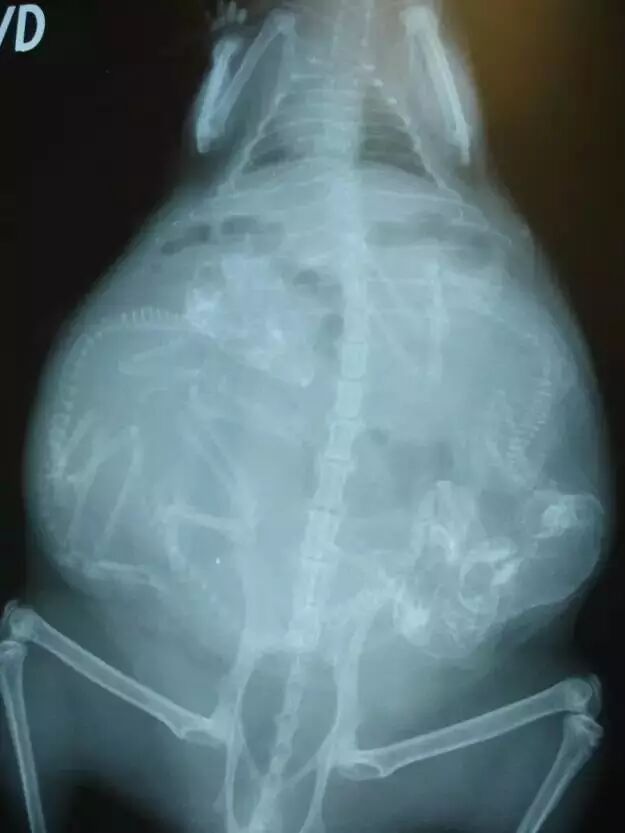

NO.1

<怀孕的狗狗>

虽然知道有些动物,

一次可以孕育很多生命,

但这么拥挤也太夸张了吧!